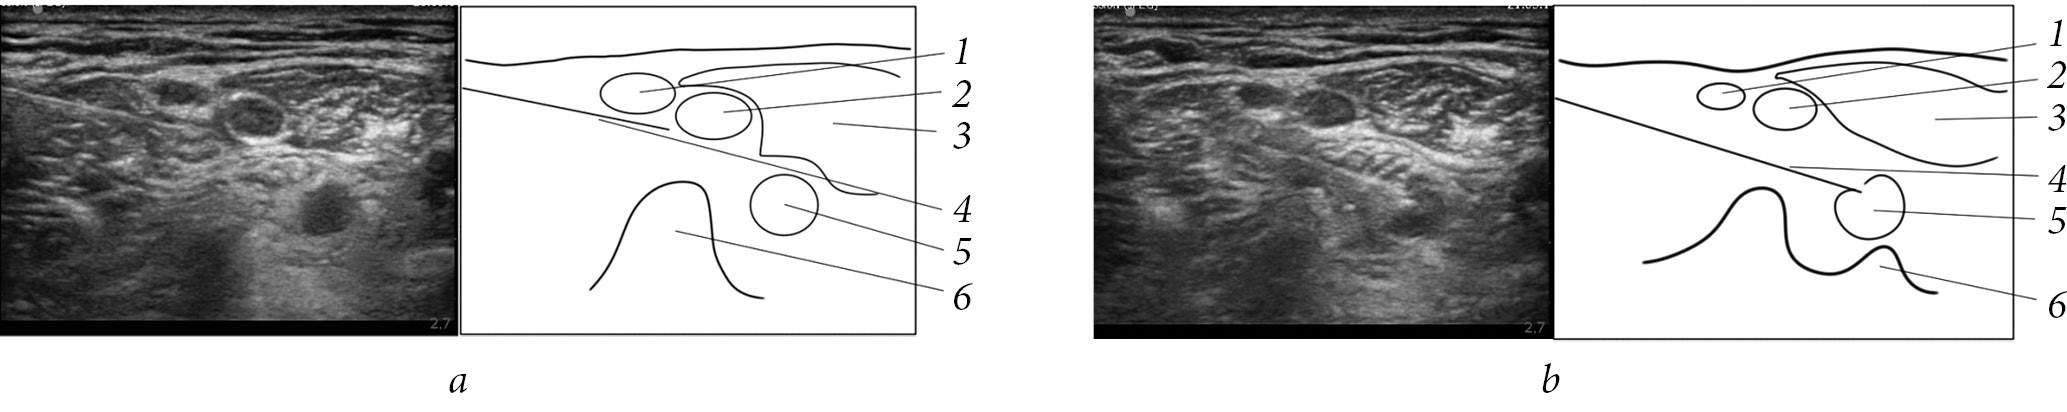

In Group 3, IBPB was performed under US navigation (Sonosite M-Turbo: 12 MHz linear sensor, transverse scanning at the level of the С6–С7 vertebrae with lateral access and long-axis imaging of the needle) and neurostimulation (Stimuplex HNS12, 0.5 mA, 1 Hz, 0.1 ms) with a selective block of the brachial plexus trunks. This was achieved by repeatedly repositioning the needle and introducing individual boluses of local anesthetic, not exceeding 0.5–1 mL, from each position. The solution was distributed around each trunk of the brachial plexus, which determined the necessary volume of local anesthetic. In total, 7–10 mL of 0.5% ropivacaine for block of the brachial plexus (Fig. 1) and 5–7 mL of 0.2% ropivacaine for the block of the superficial branches of the cervical plexus were used [15].

Fig. 1. Block of the upper, middle (a), and lower (b) trunks of the brachial plexus with lateral access: 1, the upper trunk of the brachial plexus; 2, the middle trunk of the brachial plexus; 3, the anterior scalene muscle; 4, needle; 5, the lower trunk of the brachial plexus; 6, the C7 vertebra